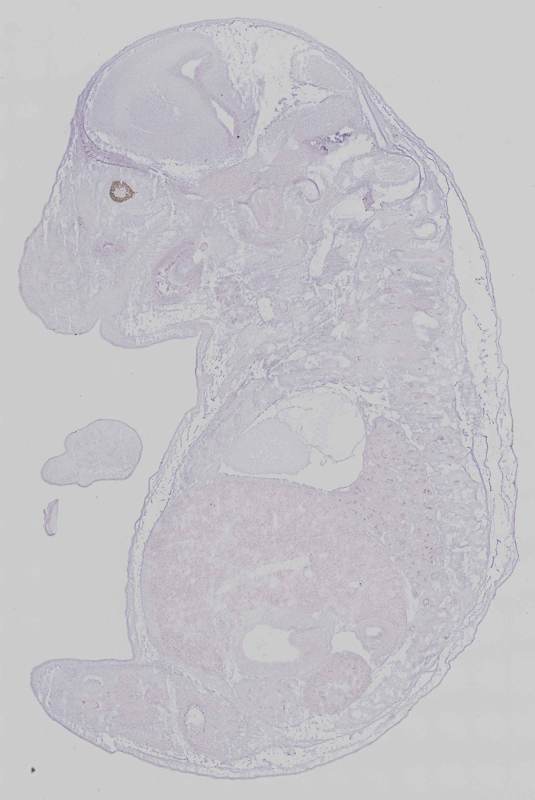

Mice homozygous for a knock-out allele exhibit prenatal lethality. Mice homozygous for an ENU induced allele exhibit preaxial polydactyly, exencephaly, microphthalmia, cleft palate, craniofacial defects, short sternum, split sternum and absent floor plate.